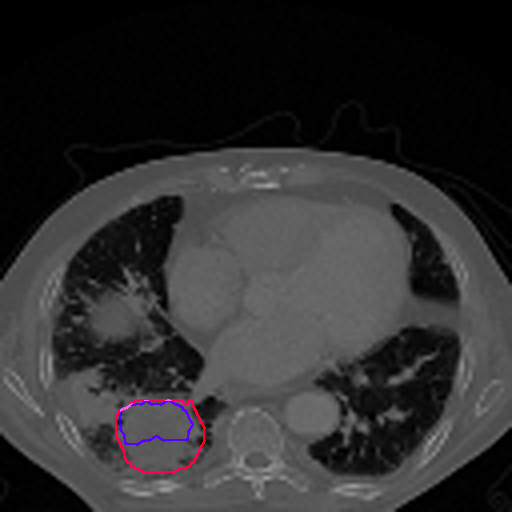

A qualitative analysis of our results reveals the strengths and weaknesses of our proposed model. In most cases, regardless of the size of the ground truth, our model predicts the tumor shapes very well. This is evident from Figure 4 where the ground truth and the prediction (by Deeply Supervised MultiResUNet) are shown in red and blue respectively. Although the tumors are in various arbitrary locations within the lung and appear in diverse sizes, the red and blue margins appear to coincide almost perfectly.